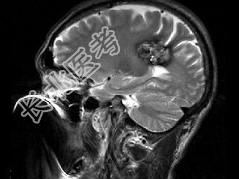

- 单项选择题男,59岁, 反复头晕头痛半年余,重体力活时头痛明显, 根据所提供图像,最可能的诊断是 ( )

A、(左顶)海绵状血管瘤

B、(左顶)室管膜瘤

C、(左侧脑室)胶质瘤

D、(左侧脑室)脉络膜乳头状瘤

E、(左顶)动静脉血管畸形